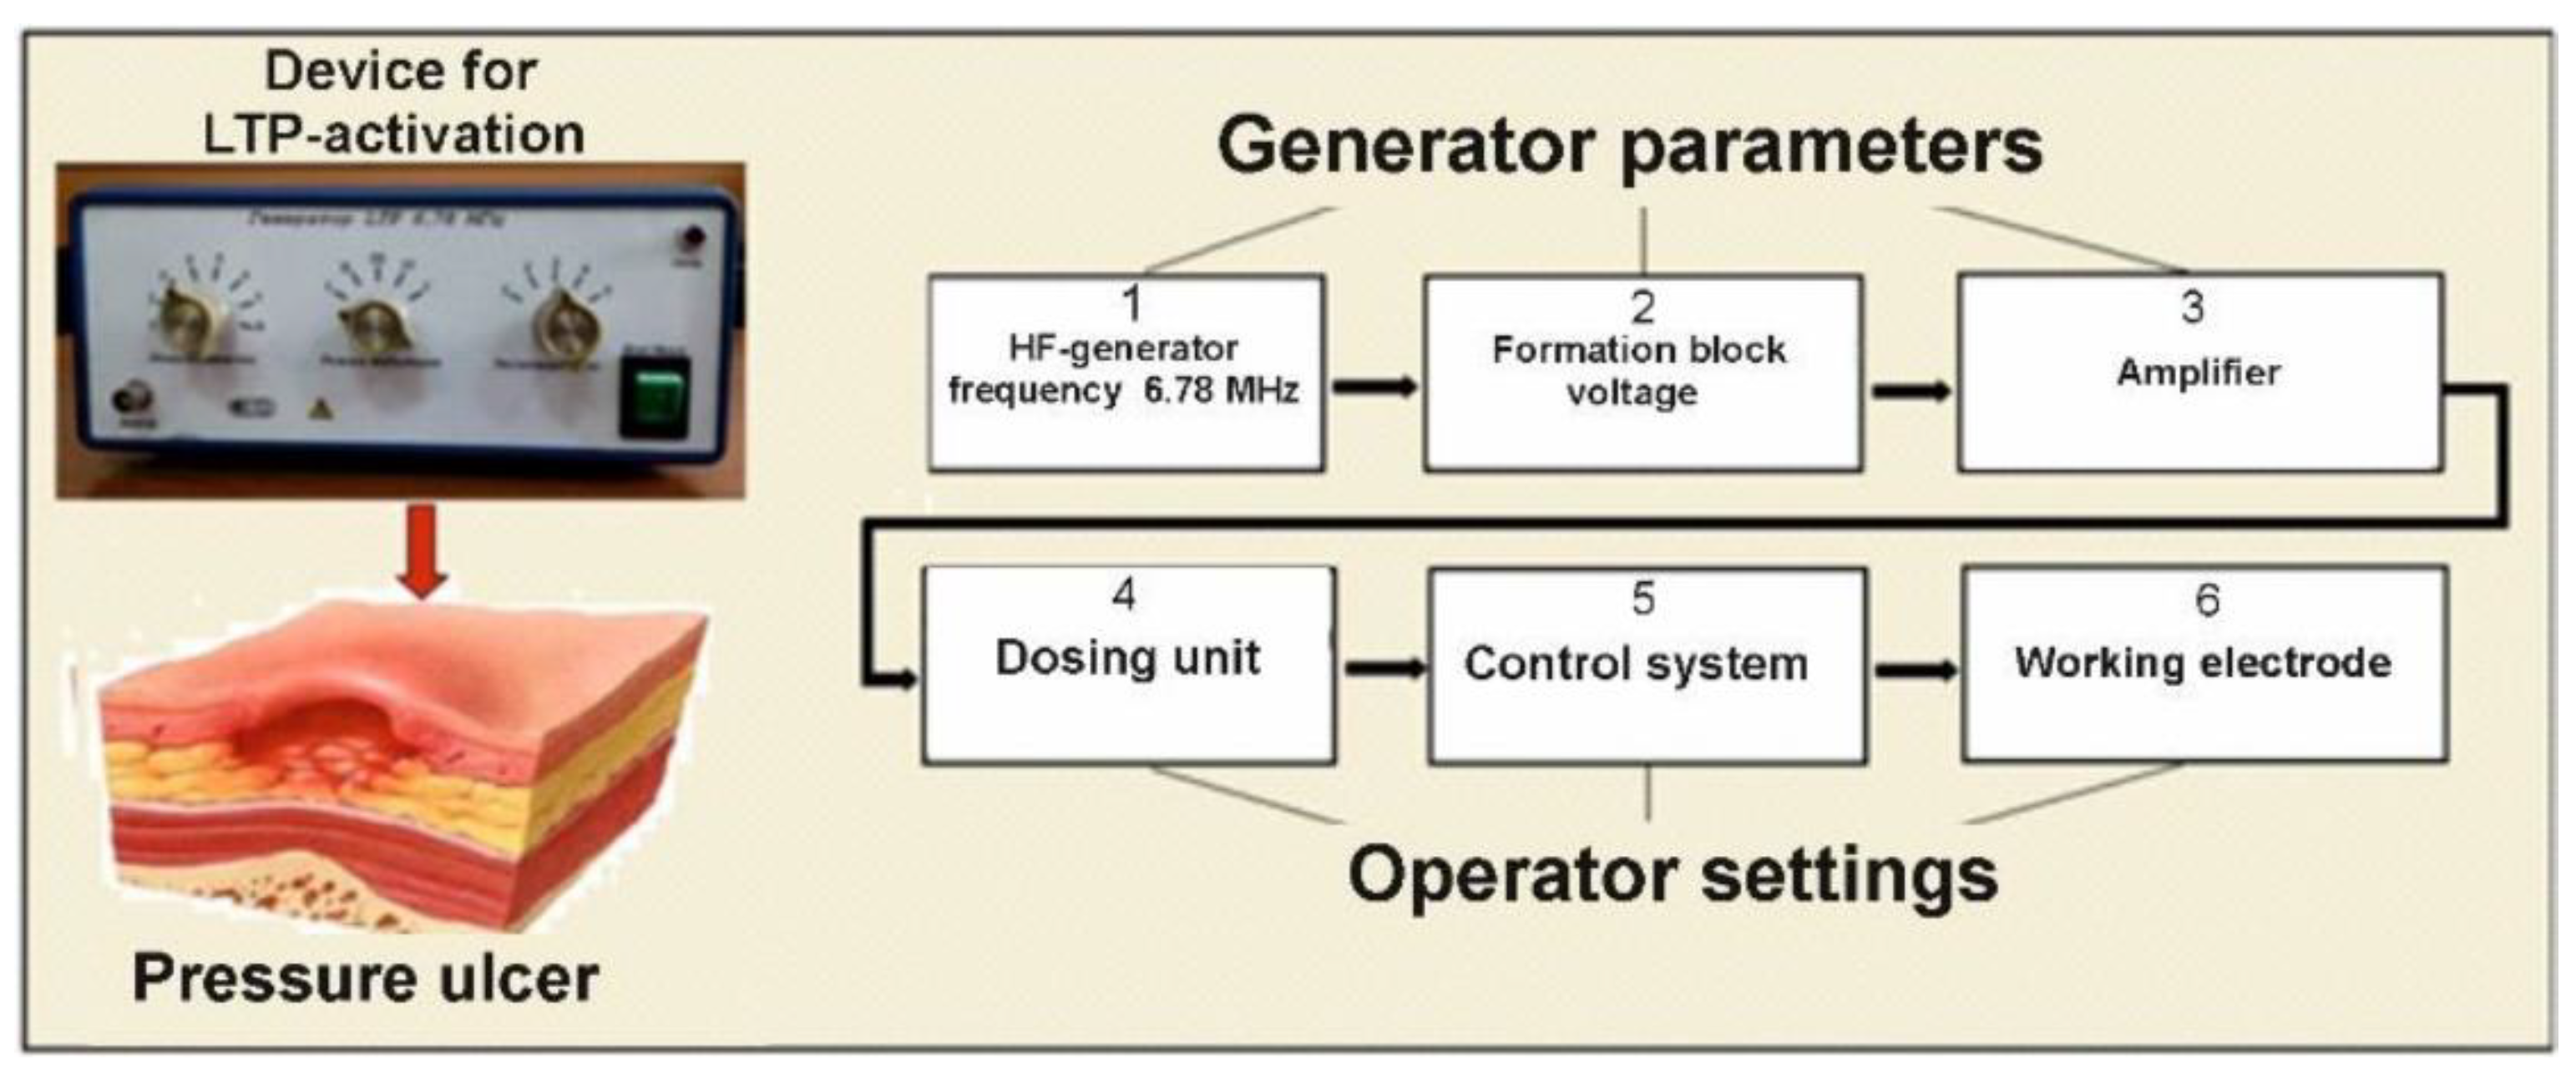

2.2. Device and Procedure for Activating the WP

- Belov, S.V.; Danyleiko, Y.K.; Egorov, A.B.; Lukanin, V.I.; Tsvetkov, V.B.; Osmanov, E.G.; Shulutko, A.M.; Altukhov, E.L.; Yakovlev, A.A. Activation of Repair Processes in Patients with Bedsores Using Pulsed Radio Frequency Currents. Biomed. Eng. 2021, 56, 169–174. [Google Scholar] [CrossRef]

- Belov, S.V.; Gudkov, S.V.; Danileiko, Y.K.; Lukanin, V.I.; Egorov, A.B.; Altukhov, E.L.; Petrova, M.V.; Yakovlev, A.A.; Osmanov, E.G.; Shulutko, A.M.; et al. Device for activating reparative processes by low-temperature plasma discharges in patients with decubitus ulcers: Parameter optimization and efficiency assessment. Med. Tech. 2022, 3, 3–9. [Google Scholar]

- Belov, S.V.; Danileiko, Y.K.; Nefedov, S.M.; Osiko, V.V.; Salyuk, V.A.; Sidorov, V.A. Specific Features of Generation of Low-Temperature Plasma in High-Frequency Plasma Electrosurgical Apparatuses. Biomed. Eng. 2011, 45, 59–63. [Google Scholar] [CrossRef]